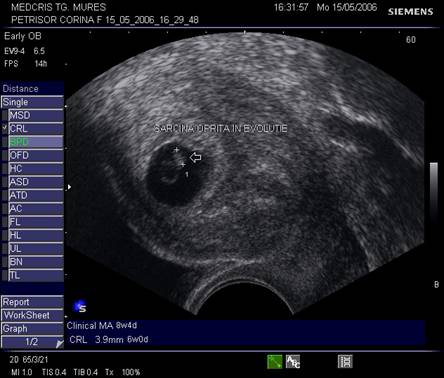

Fig nr.83 Discrepanta dintre lungimea cranio caudala embrionara (CRL intre calipere) ce corespunde la 8 saptamani si amenoreea de 12 saptamani, se remarca absenta veziculei viteline

Fig nr. 84. Discrepanta intre CRL (crown rump lenght sau lungimea craniocaudala)

si amenoree, la o sarcina oprita in evolutie